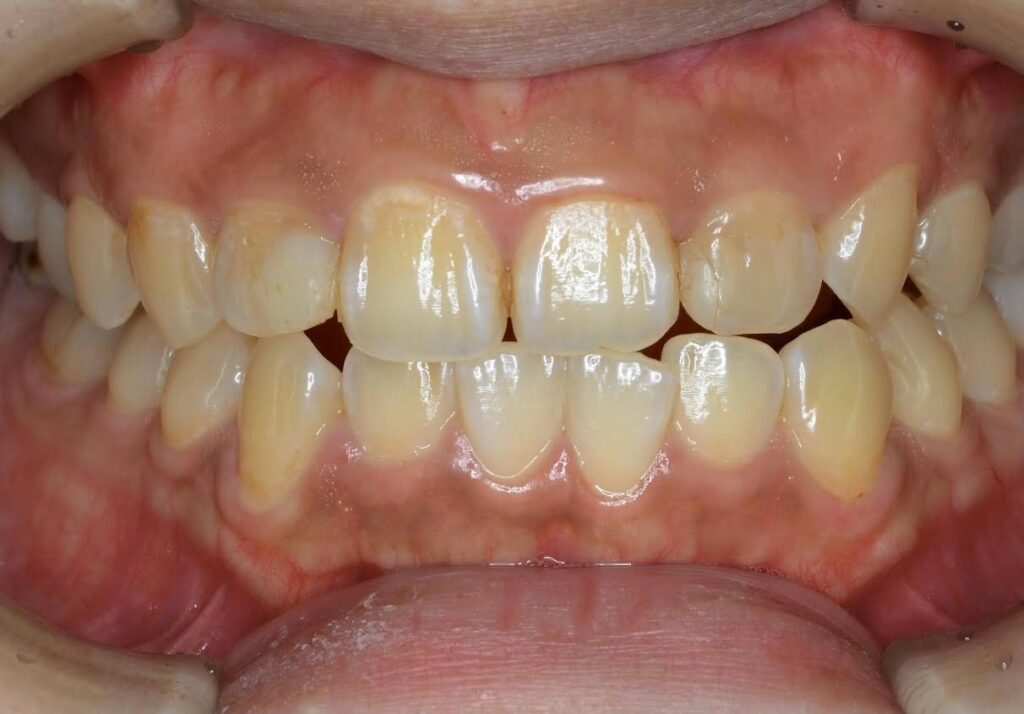

【A様】

Before

After

年齢 | 20代前半 |

性別 | 女性 |

主訴 | 上下の前歯が前に出ている。かみ合わせが悪く、食いしばりをしていて、頬の粘膜に傷ができやすい。 |

施術内容 | アライナー(マウスピース)矯正 |

治療期間 | 10ヶ月 |